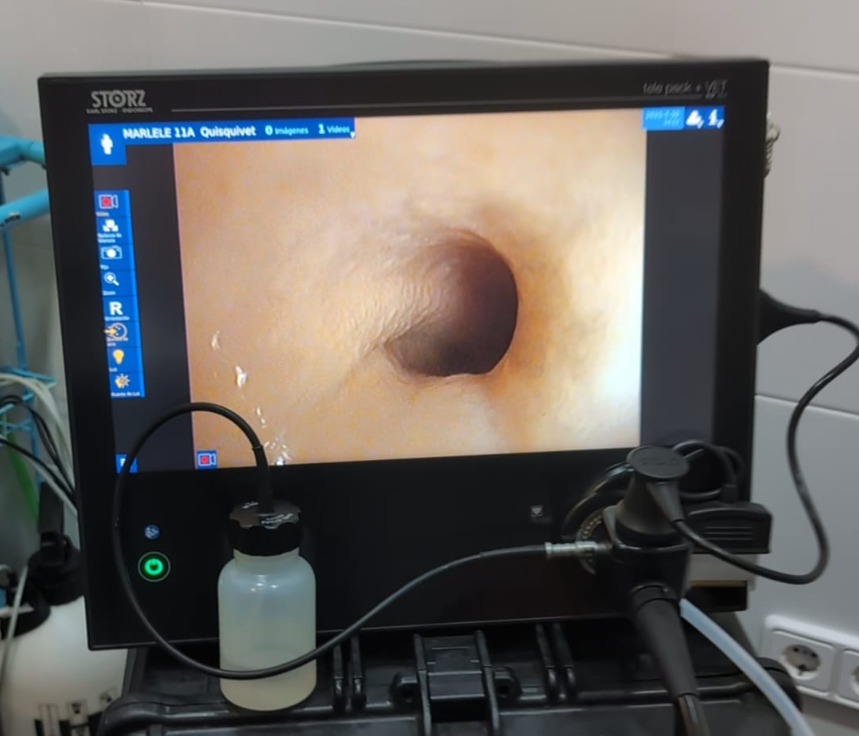

Pruebas Endoscópicas en Vigo

Las pruebas endoscópicas, como la endoscopia digestiva, la rinoscopia y la broncoscopia, son técnicas avanzadas que nos permiten explorar el interior del aparato digestivo y respiratorio de perros y gatos sin necesidad de cirugía.

Gracias a ellas podemos obtener imágenes en tiempo real, extraer cuerpos extraños o tomar muestras para un diagnóstico preciso.

En nuestra clínica veterinaria en Vigo contamos con la colaboración del especialista Javier Lista, referente en endoscopia veterinaria, lo que nos permite ofrecer un servicio experto, seguro y de máxima confianza.